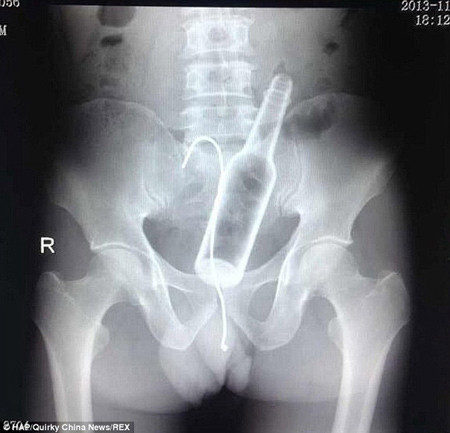

Một người đàn ông Trung Quốc đã lỡ nuốt cái chai vào bụng và trong cơn hoảng loạn ông lại nuốt thêm dây để "câu" cái chai ra ngoài.

Các bức hình chụp X-quang cho thấy cả một chai nước nằm hoàn toàn trong hậu môn của bệnh nhân này. Ông cho biết, trước đó đã mắc chứng táo bón trong một thời gian dài nhưng không làm sao chữa khỏi. Vì vậy, ông quyết định làm liều bằng cách lấy chai nước đưa vào hậu môn để “kích thích”